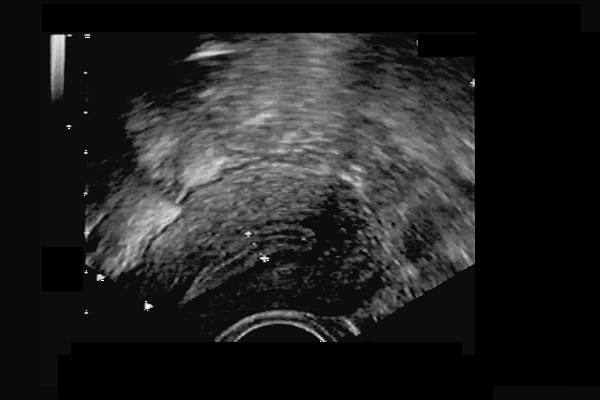

Utérus normal. Myomètre homogène - jonction endomètre/myomètre linéaire, arrondi au fond.